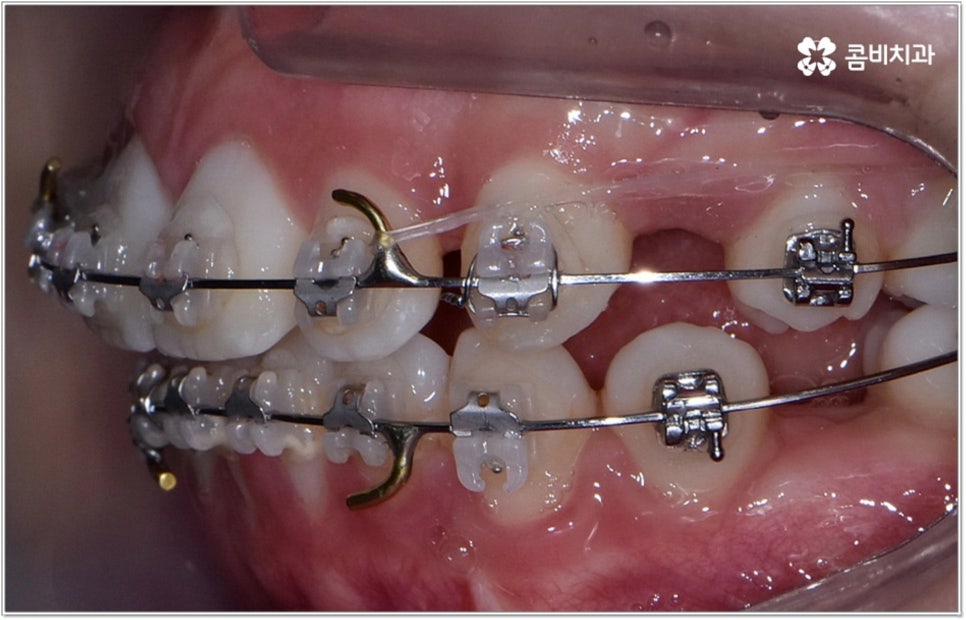

청소년기는 교우 관계에 영향을 많이 받고 외모에 민감할 때라 교정기에 대한 반감이 있을 수 있으나 바로 이때가 치아 이동에 있어 매우 중요한 시기이므로 제대로 이해할 수 있도록 차근차근 설명해 줄 필요가 있는데요. 12~15세 사이, 즉 초등학교 고학년에서 중학교 저학년 사이가 유치에서 영구치로 거의 다 교체되고 잇몸뼈가 계속해서 성장하는 나이이기 때문에 상악과 하악의 균형잡힌 발달을 유도하면서 부정교합을 바로잡고 치열을 가지런하게 만드는데 보다 빠르고 효율적인 만큼 가능하다면 이 시기를 놓치지 않는게 중요한 거예요. 물론 성인분들도 상황에 맞게 교정 치료를 진행할 수 있지만 부정교합의 종류와 정도에 따라 성장기 교정 치료를 진행하는 것이 좀 더 나은 케이스가 있으니 아이의 치열에 관심을 가지고 정확하게 알아보시는 것이 도움이 될 수 있습니다.

무리하지 않고 돌출입치아교정 과정을 진행하기 위해서는 먼저 꼼꼼한 검진 및 분석에 따른 철저한 맞춤 치료 계획 수립이 중요하다고 할 수 있는데요. 특히 3D CT 및 모르페우스 시스템을 통해 현재 아이의 치열이나 연조직, 상하악 관계 등을 자세히 살펴보고 안모 분석 후 교정 치료가 끝난 예상 모습을 시뮬레이션해서 보여주면 환아의 흥미를 유발하고 앞으로 진행될 사항에 대한 이해도를 높여줄 수 있어 긍정적인 영향을 줄 수 있으니 정밀 검진 장비를 갖추고 숙련된 의료진이 치료하는 치과에서 돌출입치아교정 과정을 진행하시길 권유드리고 있어요.

성장기 교정의 경우 턱성장 추이에 맞추어 섬세하게 치아 이동 속도를 결정해야 하므로 구강 검진 외에도 성장판 검진 등을 통해 아이의 전반적인 발달 상황에 대한 유기적인 이해를 바탕으로 치료를 하는 경험 많은 담당의 선생님께 시술을 맡기실 필요가 있습니다. 또한 이렇게 뛰어난 노하우와 기술력을 갖춘 것 뿐 아니라 사전 상담, 전 교정 과정 그리고 사후 관리에 이르기까지 지속적인 소통을 통해 불편한 점이 없는지 세심하게 살피고 개개인의 상황 및 구강 건강을 전체적으로 신경써서 케어해 주는 의료진과 함께 한다면 환아 뿐 아니라 부모님의 입장에서도 더욱 안심이 되고 좋을 거예요.

돌출입치아교정 치료에 있어서 방법이나 기간 등 자세한 사항은 환자분들에 따라 달라지는데 다른 문제 없이 치아의 각도만 앞으로 뻐드러진 경우에는 비교적 빠르고 간편하게 개선이 가능한 반면 부정교합 정도가 많이 심각하거나 골격적인 원인이 굳어진 경우 외과적 악교정수술이 병행 돼야 할 수도 있는 만큼 말씀드린 것처럼 제때 검진부터 꼼꼼하게 받아보시길 권유드리고 있습니다.